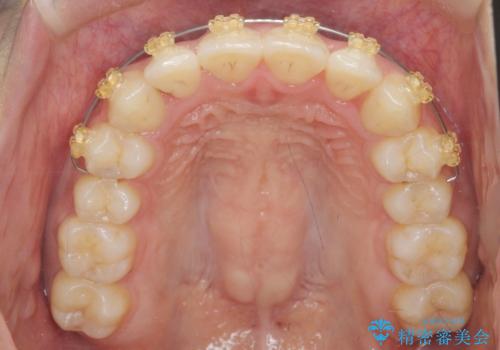

ワイヤー部分矯正を併用して治療期間を短縮 マウスピース矯正治療

- 前歯のガタつき、上下たがい違いになっている歯並び(クロスバイト)の改善を求めて来院されました。

インビザラインによる矯正治療を行いますが、クロスバイトの改善をワイヤー部分矯正で事前に行うことにより治療期間の短縮する治療計画を立案します。

上下すれ違った噛み合わせはマウスピースでは改善に時間がかかり、またねじれが残ってしまうことも多々見られます。

マウスピース矯正を行う前に、これらの症状の改善の得意なワイヤー部分矯正を行うことで治療期間を短縮し、確実にすれ違いを改善することができます。